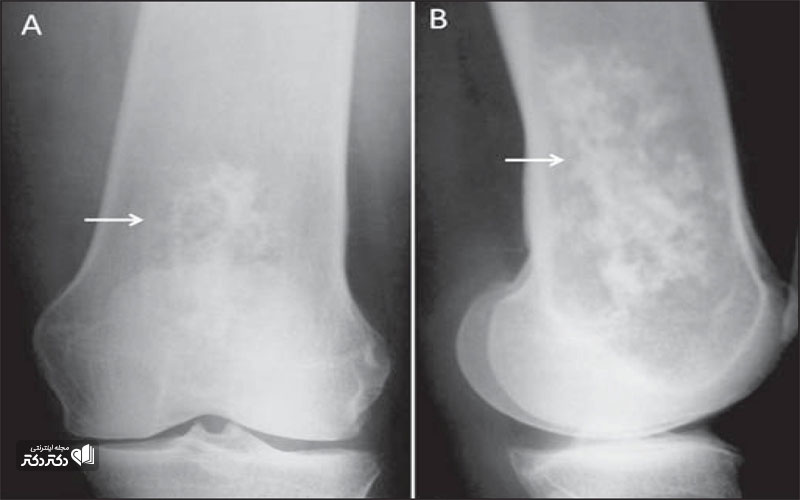

روش های عکس برداری می توانند به تعیین محل و اندازه ی تومورهای استخوان و گسترش یا عدم گسترش آن ها به سایر نقاط بدن کمک کنند. در این مقاله با علائم سرطان مغز استخوان و نیز روش های درمان آن آشنا می شوید. یک تومور رشد غیر طبیعی بافت در بدن است. سلول های توموری توانایی تنظیم کردن ندارند بنابراین سلول های بیشتری تولید می کنند و منجر به تشکیل یک توده می شوند در حالی که بسیاری از تومورها سرطانی.

تشخیص سرطان استخوان. استئوسارکوم شایع ترین نوع است که بیشتر بر کودکان و نوجوانان زیر 20 سال تأثیر می گذارد. جراحی اغلب اولین انتخاب درمانی می باشد اگرچه گاهی اوقات قطع کردن عضو لازم می باشد. درمان سرطان استخوان به نوع سرطان بستگی دارد.